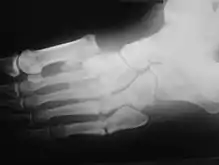

Диабети́ческая о́стеоа́ртропати́я

Является одним из тяжёлых осложнений, вызывающих стойкую потерю трудоспособности пациентов, нередко молодого возраста. Развивается у лиц с длительно некомпенсированным, лабильно текущим инсулинозависимым сахарным диабетом. Частота диабетической остеоартропатии (специфического поражения костей и суставов) колеблется от 5 до 23% всех случаев сахарного диабета[1]. Ведущая роль в патогенезе принадлежит диабети́ческой нейропати́и в сочетании с нарушениями микроциркуляции и метаболизма, приводящим к ишемическим некрозам. Клиническая картина аналогична другим нейрогенным остеоартропатиям. Локализация процесса — обычно дистальные мета́физы метатарза́льных косте́й и проксимальных мета́физах стоп, реже в процесс вовлекаются коленные и лу́чезапя́стные суставы. Изменения носят характер одностороннего поражения, редко симметричны. Сустав отёчный, безболезненный, гиперемия отсутствует, кожа холодна на ощупь. Рентгенологическая картина: изменение суставных поверхностей косте́й в виде остеопоро́за, остео́лиза, остеосклеро́за, внутрисуставных переломов, со временем развивается деформация сустава. Присоединяющаяся инфекция приводит к перифокальной гнойнонекротической реакции мягких тканей и остеомиелиту, возникают трофические язвы и свищи.